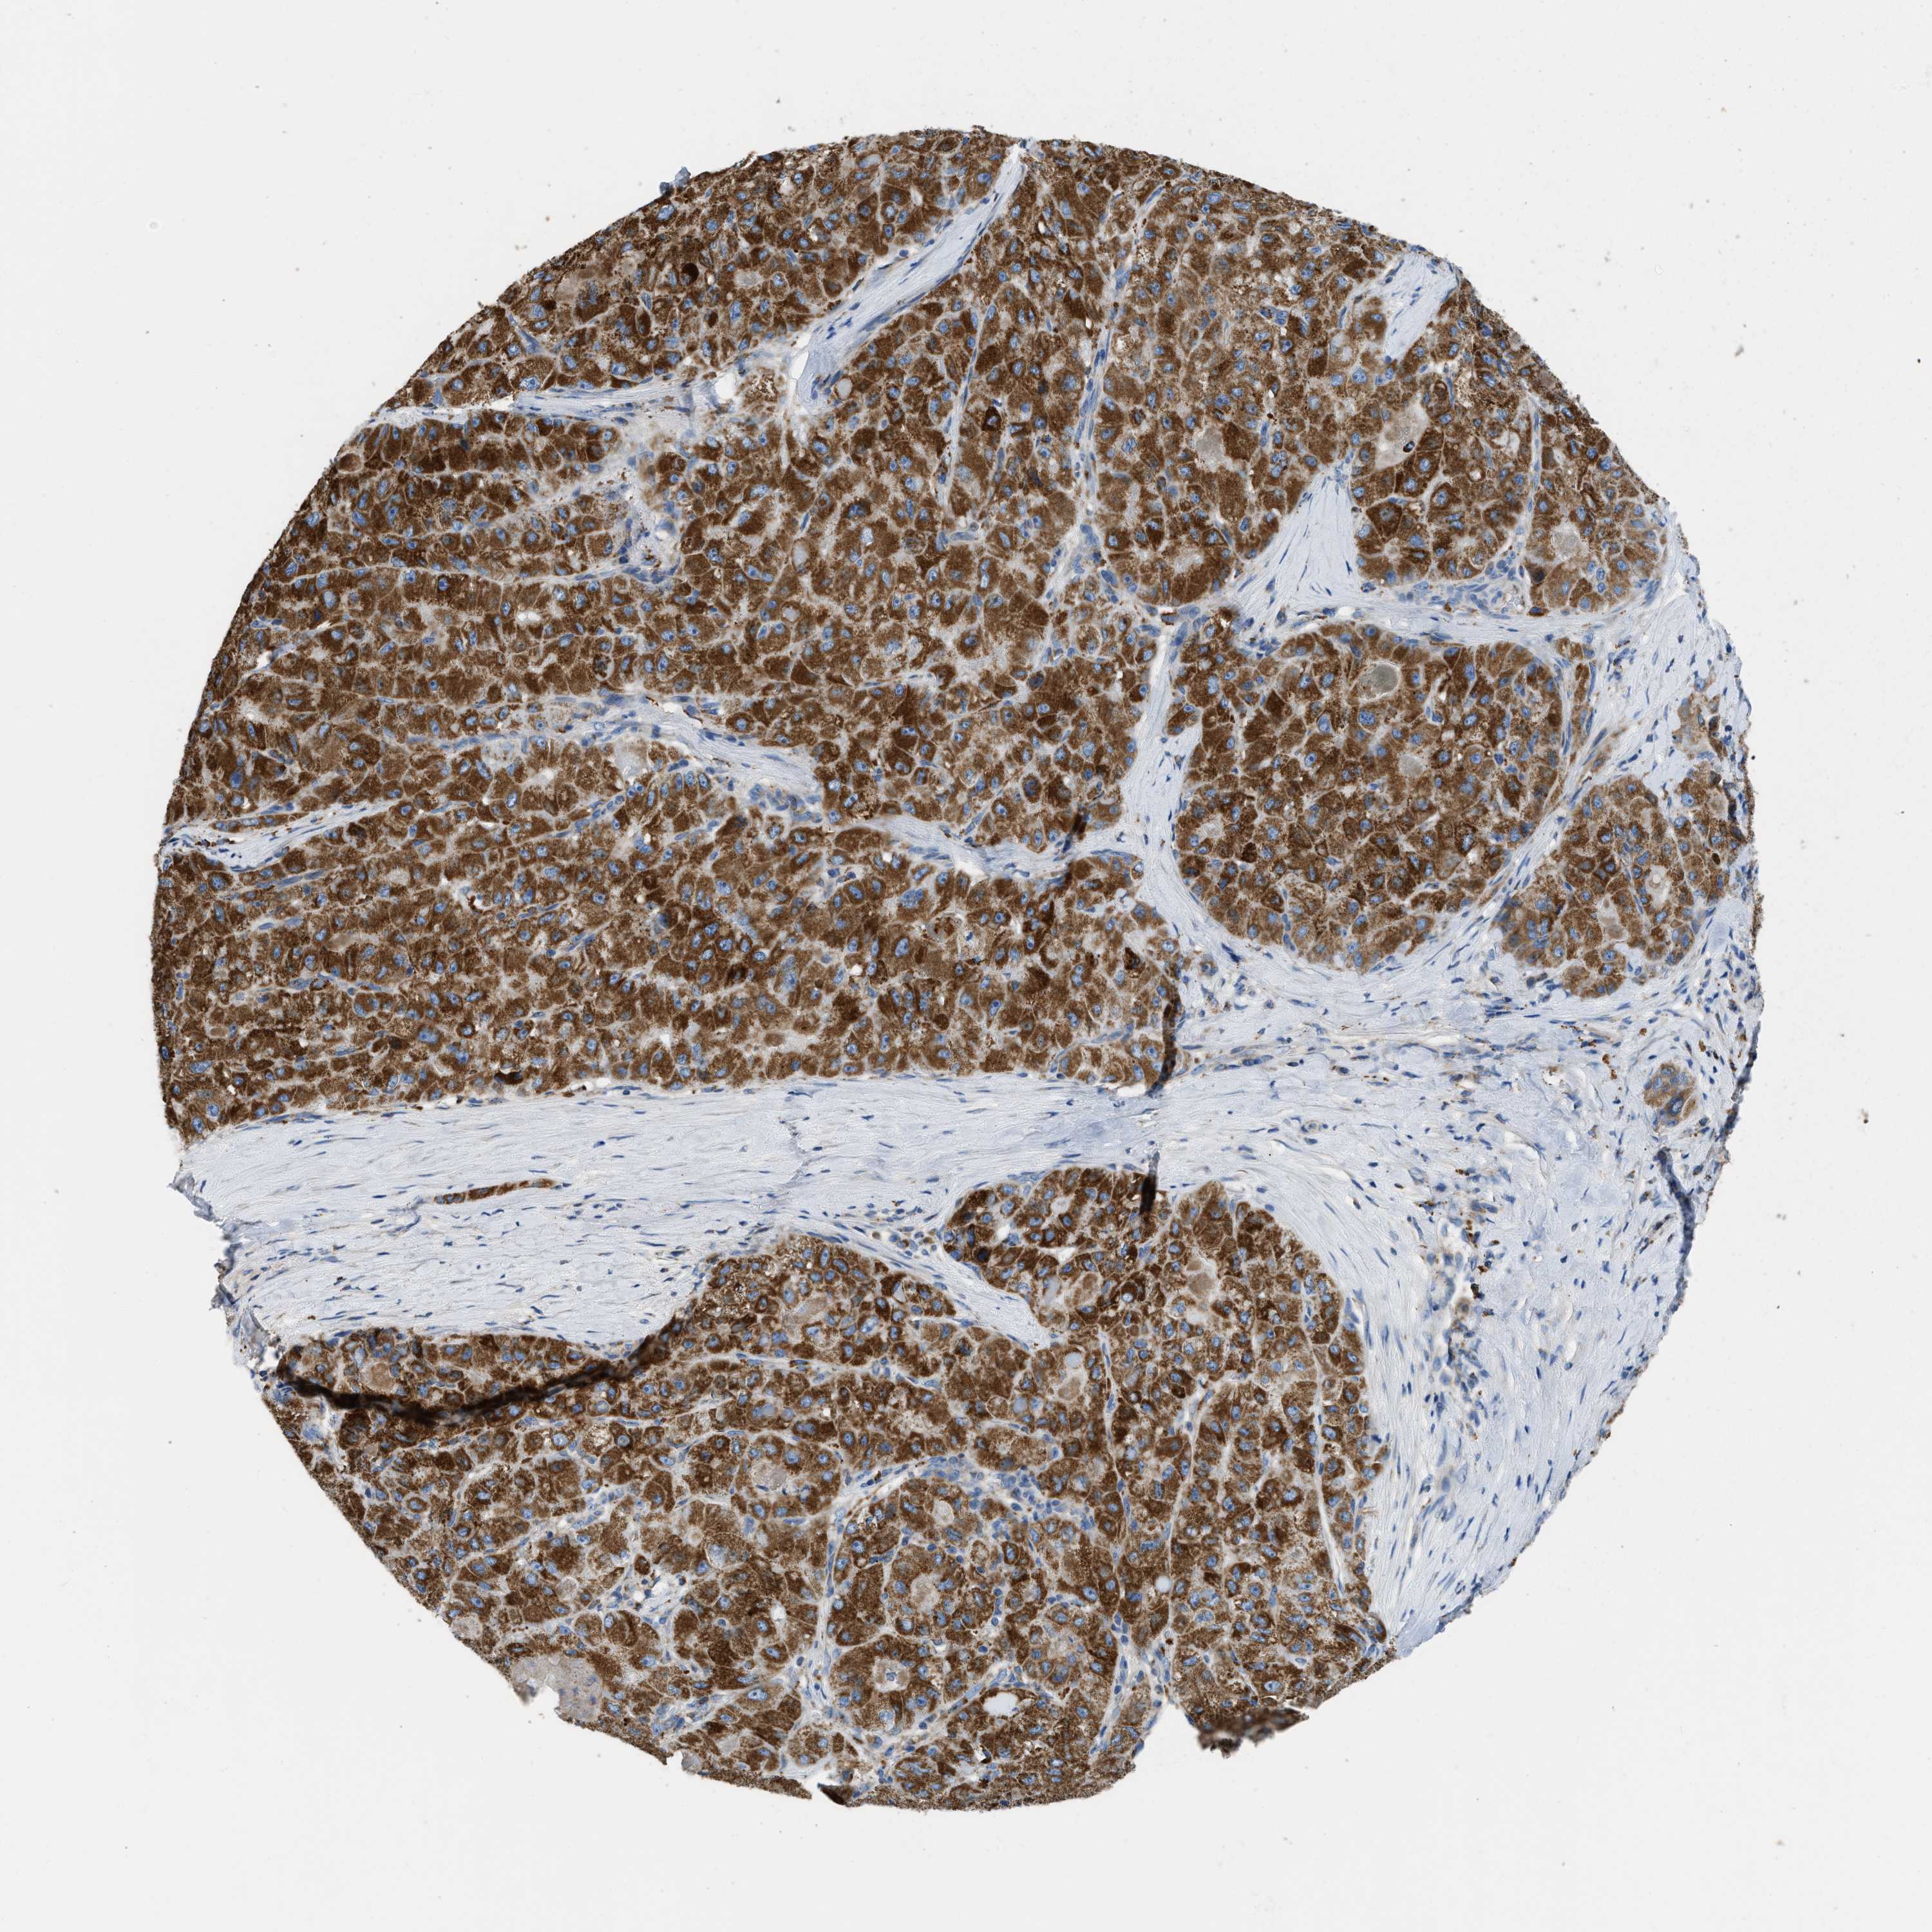

LIVER CANCER - Protein expressioni

A mouse-over function shows sample information and annotation data. Click on an image to view it in a full screen mode. Samples can be filtered based on level of antibody staining by selecting one or several of the following categories: high, medium, low and not detected. The assay and annotation is described here.

Note that samples used for immunohistochemistry by the Human Protein Atlas do not correspond to samples in the TCGA dataset.

Antibody stainingi

Antibody staining in the annotated cell types in the current human tissue is reported as not detected, low, medium, or high, based on conventional immunohistochemistry profiling in selected tissues. This score is based on the combination of the staining intensity and fraction of stained cells.

Each image is clickable and will lead to virtual microscopy that enables deeper exploration of all samples and also displays staining intensity scores, fraction scores and subcellular localization as well as patient and tissue information for each sample.

Antibody HPA018997

Staining

High

Medium

Low

Not detected

Intensity

Strong

Moderate

Weak

Negative

Quantity

>75%

75%-25%

<25%

None

Location

Nuclear

Cytoplasmic/membranous

Cytoplasmic/membranous,nuclear

Cholangiocarcinoma

Carcinoma, Hepatocellular, NOS